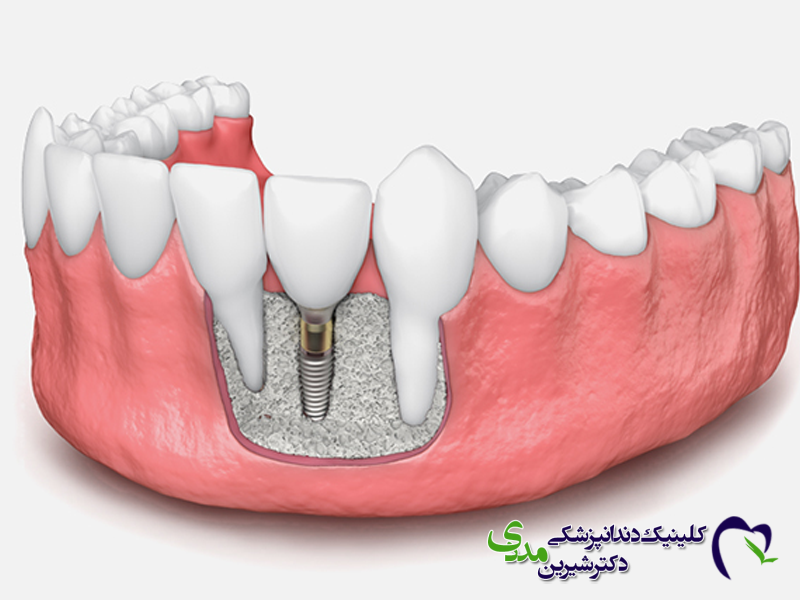

ایمپلنت چیست؟

همانطور که بارها اشاره شده است، ایمپلنت دندان یک پایه ی تیتانیومی است که طی یک جراحی درون استخوان فک قرار می گیرد و نقش ریشه ی دندان را بازی می کند. پس از جوش خوردن ایمپلنت به استخوان، یک تاج دندانی (روکش) بر روی آن سوار می شود. ایمپلنت ها به صورت واحد واحد جایگزین دندان های از دست رفته می شوند و ثابت هستند.

ایمپلنت: هر ایمپلنت یک دندان واحد را نگه می دارد. روکش ها ثابت هستند و فقط توسط دندانپزشک قابل برداشتن هستند. ظاهری کاملاً طبیعی و مشابه دندان های واقعی دارند.

ایمپلنت: ثابت هستند و دقیقاً مانند دندان طبیعی در دهان قرار می گیرند. پس از نهایی شدن، حس و عملکردی مشابه دندان اصلی دارند.